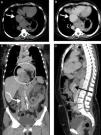

Angiotomografia de tórax, abdome e pelve sem contraste em A e com contraste na fase venosa em B, C e D, demonstrando veia cava inferior com dilatação aneurismática na região proximal junto à desembocadura na aurícula direita, atingindo no maior calibre 56mm (seta branca reta). As drenagens das veias hepática média, direita e esquerda, ocorrem na porção aneurismática, que está herniada para a região torácica com parte do segmento hepático (círculo branco). Distalmente ao aneurisma, na porção intra‐hepática, a veia cava inferior tem calibre muito reduzido, praticamente colapsada, por uma distância de 35mm (seta preta). A veia cava inferior assume aspeto e calibres normais apenas na região sub‐hepáticas, recebendo a drenagem das demais veias abdominopélvicas (seta branca curva).

Mulher de 62 anos, submetida a exame de controle por resseção de tumor renal a esquerda há dois anos, referindo dispneia aos médios e grandes esforços. A angio‐TC de tórax, abdome e pelve demonstra veia cava inferior (VCI) com dilatação aneurismática idiopática na região proximal junto a aurícula direita, atingindo no maior calibre 56mm – classificação Gradman e Steinberg 1 (Figura 1). As drenagens das veias hepáticas média, direita e esquerda, ocorrem na região aneurismática, que está herniada para a região torácica com parte de segmento hepático. Distalmente ao aneurisma, na porção intra‐hepática, a VCI tem calibre muito reduzido, praticamente colapsada, por uma distância de 35mm. A VCI assume aspeto e calibres normais apenas na região sub‐hepática, recebendo a drenagem das demais veias abdominopélvicas.